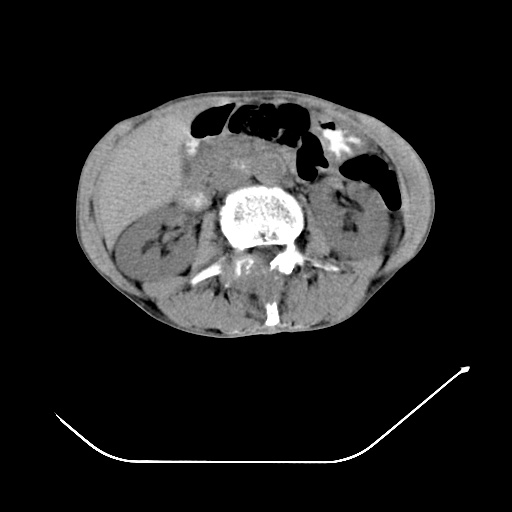

以下是引用zsl6918在2008-8-25 21:55:00的发言:[br]符合右肺周围性肺癌并肺内转移,左肺结核球。双肺肺气肿。腰椎附件转移。

以下是引用随光逐影在2008-8-25 22:03:00的发言:[br]1)考虑右肺下叶周围性肺癌并肺内转移,腰椎附件转移。2)左上肺结核(结核球形成)。3)双肺肺气肿(多发肺大泡形成)。4)双肺门区及纵隔内多发淋巴结钙化。